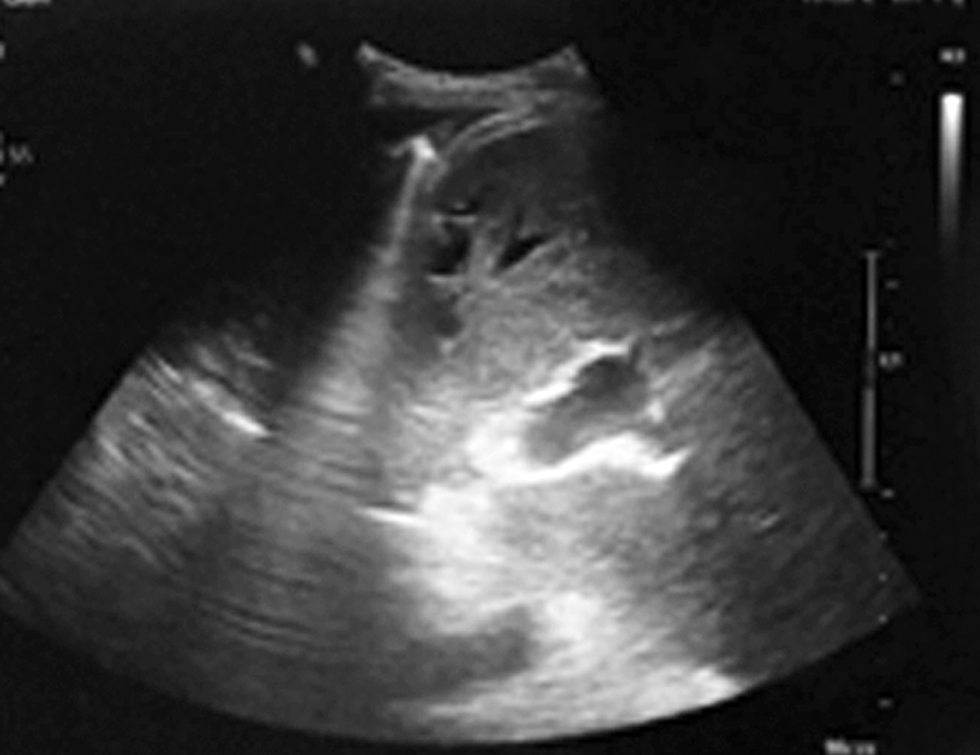

The ultrasound examination in September 2022 was with normal hepatic parenchima, patent vascular anastomosis and without collection or ascities (fig. 10).

Figure 10 - Ultrasound examination - no more perihepatic collection (September 2022)